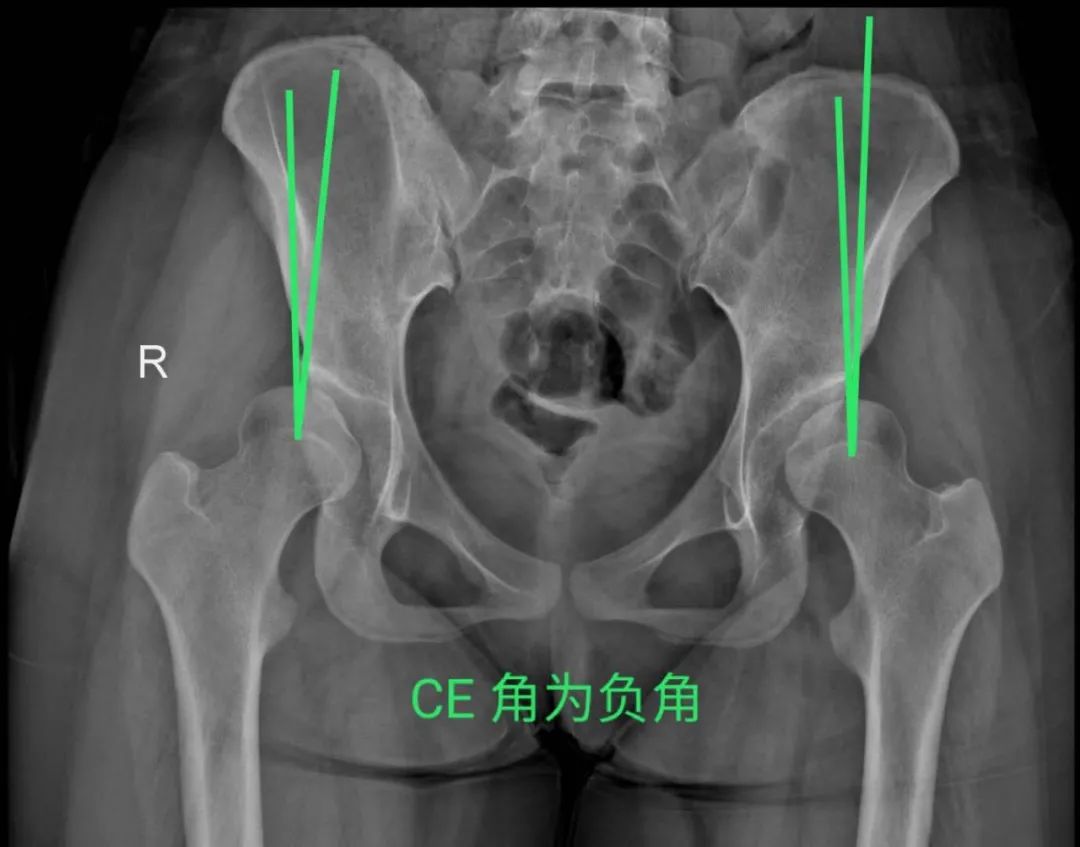

今年15歲的孫某,出現(xiàn)雙側(cè)髖部疼痛,呈持續(xù)性隱痛,只采取口服藥物的保守治療,但是疼痛未見減輕反而愈演愈烈,于是到誠德骨科醫(yī)院集團(tuán)(市中院區(qū))尋求專家的幫助,經(jīng)過多方檢查和論證后,劉德俊院長診斷為:

先天性多發(fā)性骨骺發(fā)育不良,并決定為其實(shí)施“髖臼周圍截骨術(shù)”。

據(jù)了解,髖關(guān)節(jié)發(fā)育不良是引起繼發(fā)性髖關(guān)節(jié)炎的重要致病因素之一,髖臼周圍截骨術(shù)能夠有效改善髖臼覆蓋、增加負(fù)重關(guān)節(jié)面,內(nèi)移髖關(guān)節(jié)的旋轉(zhuǎn)中心,從而減小髖關(guān)節(jié)負(fù)重面軟骨應(yīng)力,達(dá)到預(yù)防和推遲骨關(guān)節(jié)炎發(fā)生的目的。